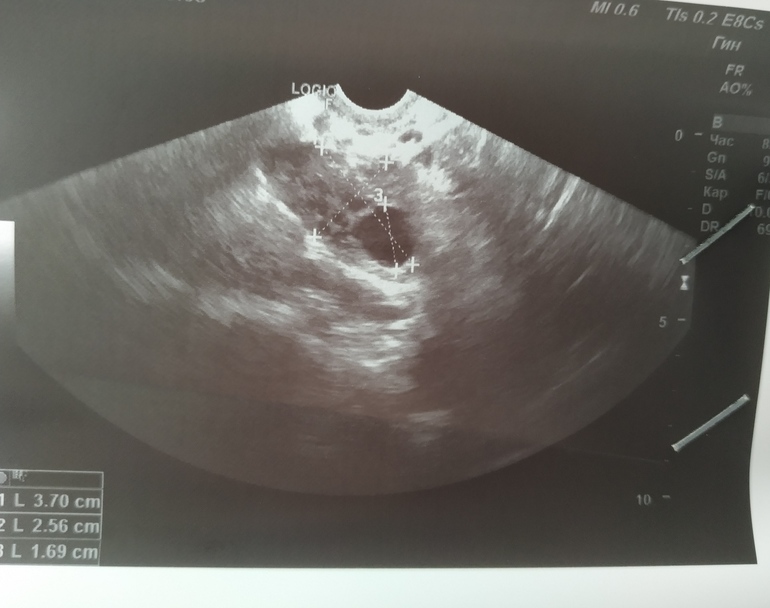

Уже второй месяц отслеживаю всеми методами: БТ, тесты, ЯБ, ощущения и УЗИ. То ли тесты врут, то ли что? 🤯🤯🤯

У меня в прошлом цикле после ЗБ были две овуляции на 25 и 33 ДЦ, подтвержденные УЗИ и БТ. Я собственными глазами видела ЖТ на УЗИ🤯🤯 а тестовая полоска не дотягивает до контрольной

Всего тот цикл был 46 дней